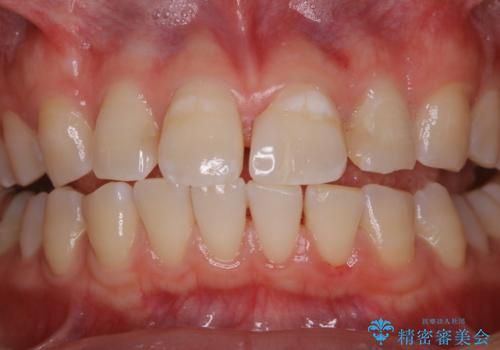

- これからインビザラインでのマウスピース矯正が始まるので、歯石取りをしてほしいとのことでした。

PMTC60分コースを行いました。

歯並が、がたついている場合はなおさら汚れが溜まりやすいです。矯正治療前や矯正中、定期的にPMTCをすることで、矯正治療中の歯肉トラブルを防ぐことにつながります。